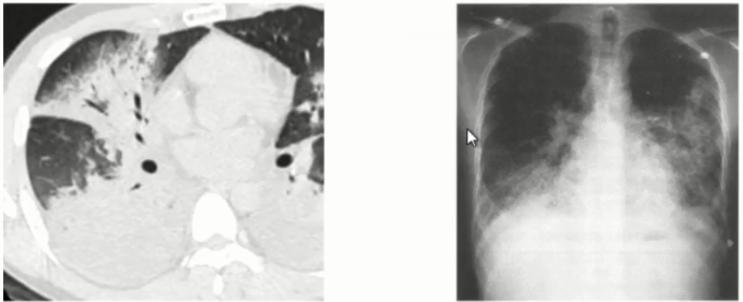

病例2

男性,33岁,既往身体健康,发热6天入院,无咳嗽、咳痰、咯血、呼吸困难。

日最高体温38.4℃,伴头痛、全身乏力,肺CT示双肺多发结节影,予头孢克肟、美洛西林舒巴坦、布洛芬、奥司他韦等治疗效果欠佳。

血常规WBC 10.63 G/L,N 0.816,L 0.101。CRP 7.42mg/dl,肺炎支原体抗体<1:40,SARS-CoV-2核酸及抗原筛查试验(-)。

入院后情况

• 肺炎支原体抗体1:320

• 左氧氟沙星0.5 QD 口服治疗后体温正常

图2 影像表现以多发肺结节合并晕征,类似于真菌感染